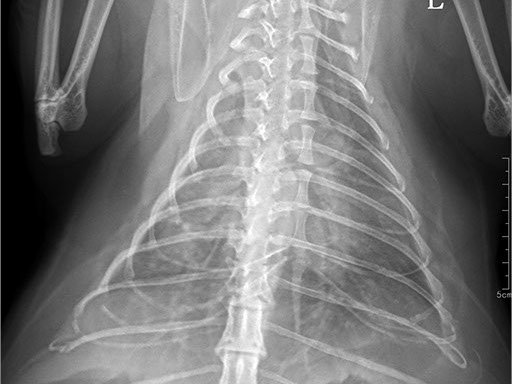

Цифровая рентгеновская установка ASR-6150C поставляется с мобильным столом пациента и комплектом рентгенопрозрачных анатомических ложементов всех размеров, видов и пород домашних животных.